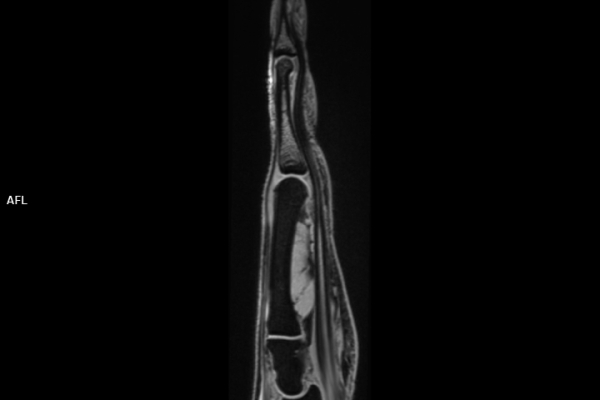

Detailbild MRT

• Muskuloskelettale Bildgebung

• Neuroradiologie

Die MRT (Magnetresonanztomographie) arbeitet mit Magnetfeldern und Radiowellen und eignet sich besonders für Untersuchungen der Weichteile wie Gehirn, Muskeln oder Gelenke. Die CT (Computertomographie) nutzt Röntgenstrahlen und liefert schnelle, hochauflösende Bilder, insbesondere für Knochen, Lunge oder innere Organe. Die Wahl der jeweiligen Untersuchung richtet sich an das individuelle Krankheitsbild und wird bei der Überweisung festgelegt.